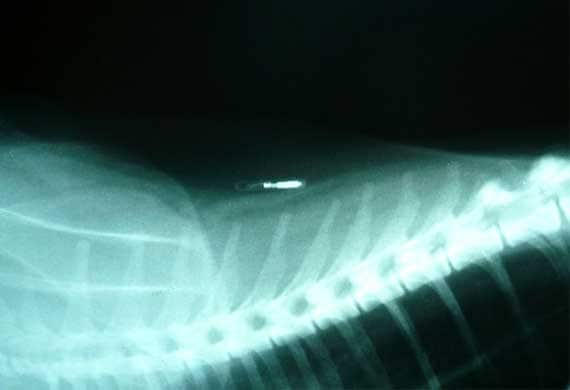

#3 Microchipping

The Humane Society defines microchips as “a tiny transponder about the size of a grain of rice that uses radio waves to transmit information about your pet.” If you and your pet should become separated and it ends up in a shelter, the employees will use a scanner to detect the registry information and phone number of the microchip company your pet is registered with. A microchip is usually placed between your pet’s shoulder blades.